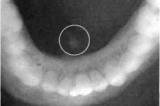

Բերանի խոռոչի մեջ արտազատիչ ծորաններով բացվում են երեք զույգ մեծ թքագեղձերը՝ հարականջային, ենթածնոտային և ենթալեզվային: Բացի այդ, բերանի խոռոչի լորձաթաղանթի մեջ...